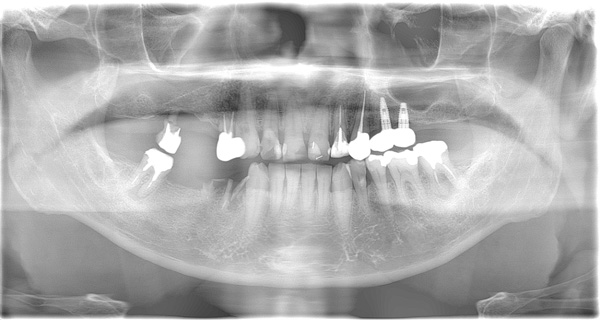

| 年代・性別 | 50代 女性 |

|---|---|

| 主訴 | 左上のブリッジがグラグラして外れそう |

| 治療期間 | 約18ヶ月 |

| 費用 | 1,600,000円 |

| 治療内容 | インプラント、骨造成、サイナスリフト、セラミック修復 |

| 治療に伴うリスク | インプラント周囲炎 セラミックの破折、脱離 |